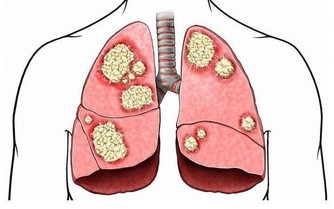

②惡性腫瘤淋巴結轉移,已經出現癌細胞轉移的淋巴結,質地比較硬,表面會有凹凸不平的樣子,還會和皮膚發生粘連,一般沒有疼痛感;

③淋巴結結核,當淋巴結內部出現壞死時,破爛潰瘍後就會形成瘻管。

這個可能和很多疾病有關,例如傳染性單核細胞增多症、淋巴瘤、急慢性白血病、系統性紅斑狼瘡等。這種類型的淋巴結腫大會遍布全身,大小不等,不粘連,活動性好。